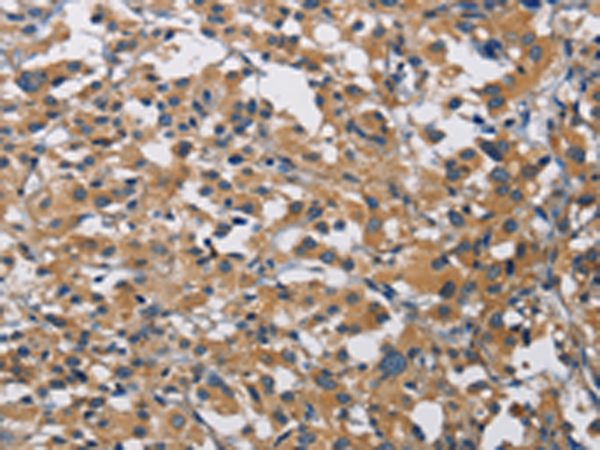

分类: 科研抗体货号: P08018别名: MSS4; STM7应用: IHC反应种属: Human, Mouse, Rat